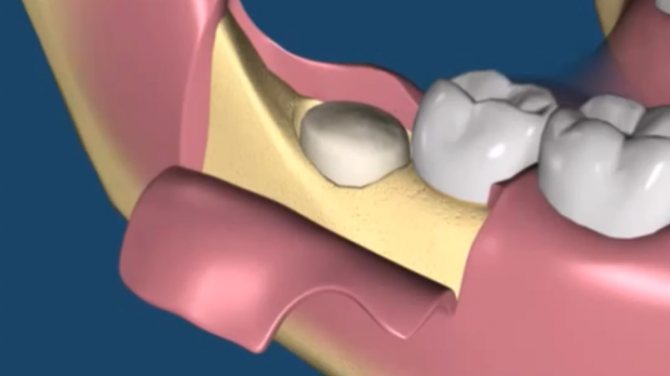

Лунка зуба с одним корнем зарастает быстрее (16-18 суток), чем ранка после удаления многокоренного зуба (19-23 суток). Если рана получилась большой (это происходит после удаления зубов со сложной корневой системой, непрорезавшихся и аномально стоящих зубов), на нее накладывают швы.

Как проводится эта методика – если лунка пустая, то под анестезией костные стенки лунки выскабливаются кюретажной ложкой, чтобы создать кровотечение и лунка заполнилась кровью (видео 3). Если же лунка заполнена грануляциями, то их тщательно выскабливают, т.е. делают тот же кюретаж (видео 4). Далее в обоих случаях после того как лунка заполняется кровью – в глубь лунки кладется противовоспалительное лекарство (Альвожель), а на слизистую накладывается несколько швов, чтобы сблизить края раны. Сразу же назначаются антибиотики.

Если операция была сложной, повреждена большая площадь, края десны сильно искромсаны, врач накладывает швы. Они помогут удержать сгусток в альвеоле.